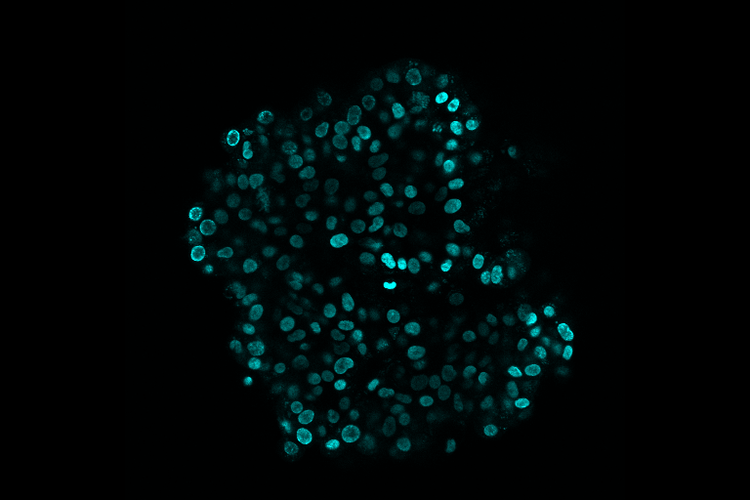

• バイオイメージング

FV3000

FLUOVIEW™ FV3000RS共焦点レーザー走査型システム

高速現象や生理学的事象のライブ観察と記録を可能にするハイブリッドレーザー走査型ユニットでは、ガルバノメータースキャナーを精密スキャンに、レゾナントスキャナーを広視野の高速イメージングに使用しています。

IXplore Live

IXplore™ Liveイメージングシステム

生理学的実験における細胞生存を強化する、IXplore Liveシステムでは、光褪色が低減し、厳しい生理条件下でサンプルを良好な状態で維持しやすくなります。